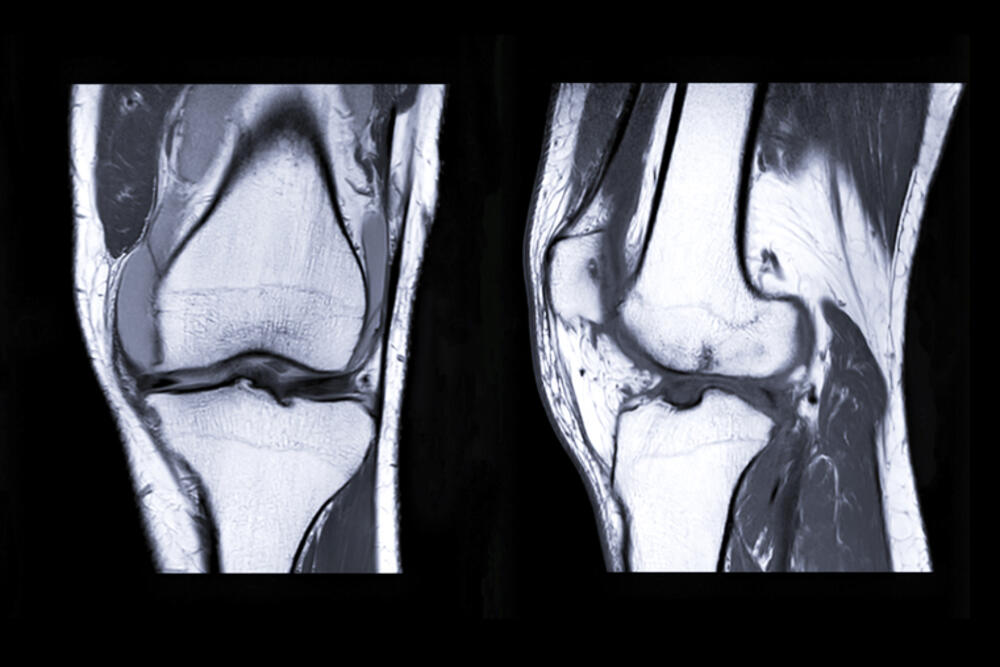

Oštećenja hrskavice su unutarzglobno oboljenje koje se u savremenoj medicinskoj praksi dijagnostikuje jedino i isključivo, neinvanzivnim pregledom magnetnom rezonancom. Te patološke promjene mogu biti posljedica traumatskih promjena, kod sportista ili drugih povreda zglobova, patoloških upalnih ili metaboličkih oboljenja i, uobičajeno, kao posledica starenja. U svim ovim slučajevima se stepen oštećenja određuje pregledom magnetnom rezonancom, a u poliklinikama Hipokrat raspolažemo sa MR poslednje generacije. Na osnovu tog pregleda se određuje terapijski protokol, u kojem su glukozamin sulfati jedan od temelja regenerativne terapije.

Magnetna rezonanca hrskavice koljena.

Magnetna rezonanca hrskavice koljena.foto: Hipokrat